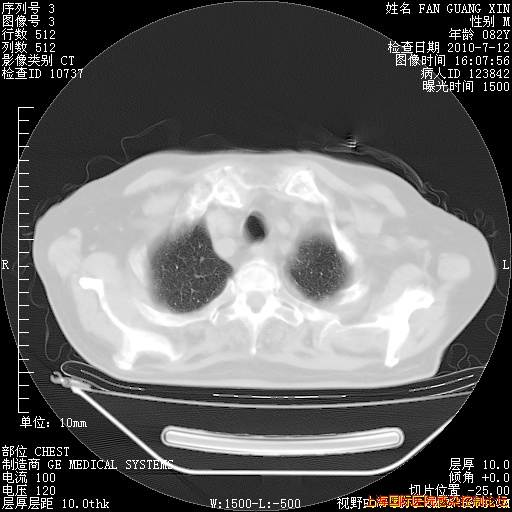

6月12日纵膈窗

今天复查CT

今天CT

整整相隔30天的肺部CT好像有所好转啊。甲强龙减量第3天,需要观察体温。

海管,自昨日你和我通完话后,不知您岳父消化道症状有无缓解?体温怎样?阅读7.12日胸部ct,个人认为目前激素治疗是有效的,甲强龙减量是适宜的。因在抗痨治疗,需密切观察肝功、肾功能和血常规。不过,老年、长期住院和大量使用激素,很担心菌群失调发生